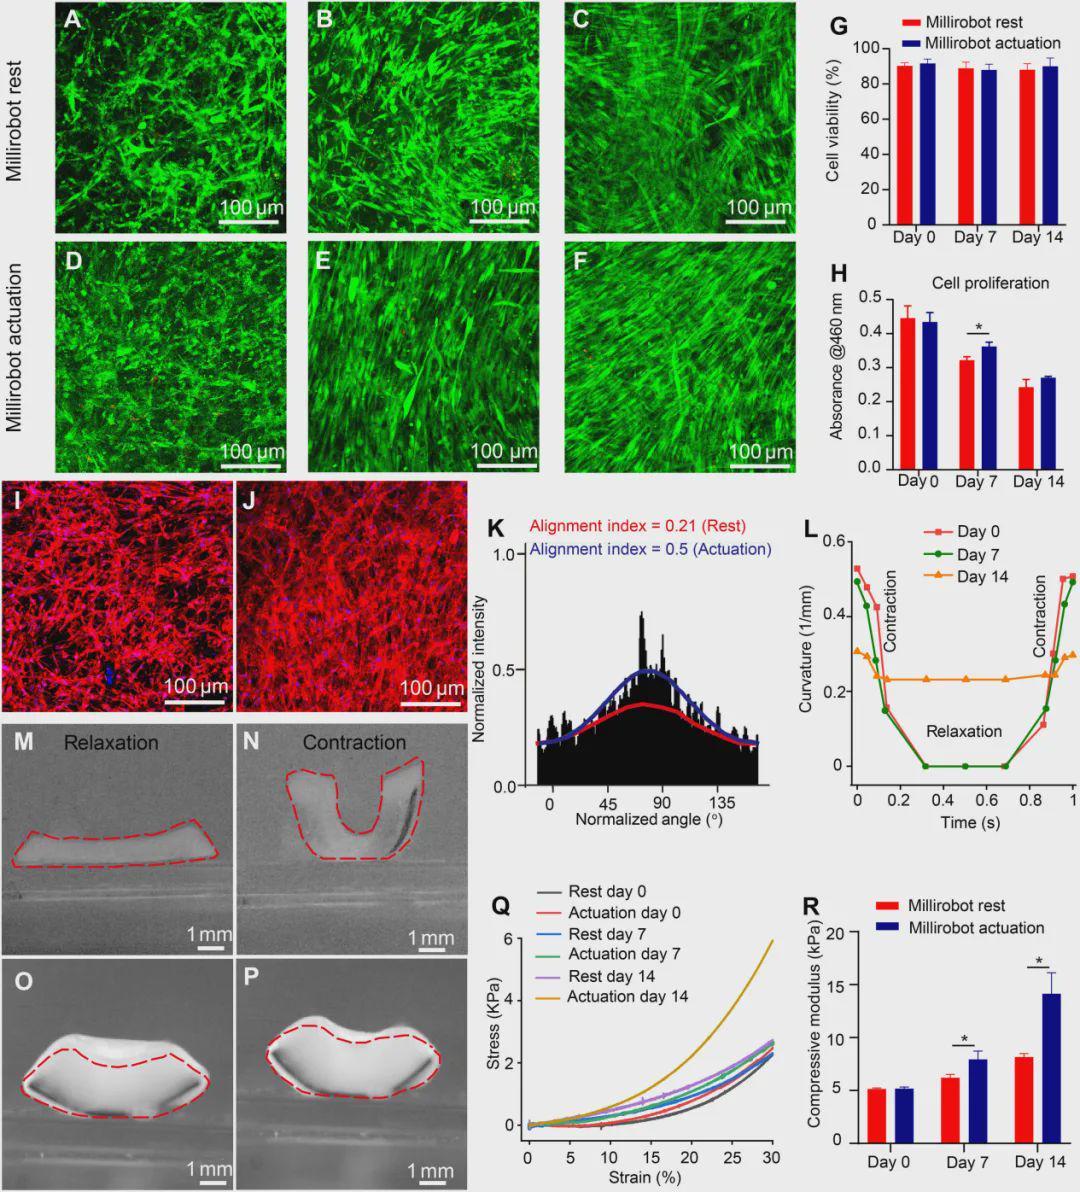

研究团队以小鼠成肌细胞(C2C12)、人骨髓间充质干细胞(hMSCs)、美国国立卫生研究院(NIH)小鼠成纤维细胞(3T3)等为模型,系统验证了机械刺激对细胞行为的积极影响。

1.生存与增殖:不仅活得好,还长得快

存活率高:无论是否施加机械刺激,细胞在机器人上的存活率均超过85%。

增殖增强:在最佳参数(1Hz频率,每天刺激1小时)下,机械刺激组的细胞增殖活性显著高于静止组。六边形孔结构因其较大的细胞生长面积和厚度,表现最优。

定向生长:在机械刺激的引导下,细胞倾向于沿应力方向定向排列,为后续功能化奠定了基础。

>2D细胞片软穿孔微型机器人的生物相容性以及原位机械刺激对C2C12细胞生长的影响

>2D细胞片软穿孔微型机器人的生物相容性以及原位机械刺激对C2C12细胞生长的影响

3.从2D到3D:构建具有机械响应的活体组织

为了修复更大体积的组织缺损,团队进一步开发了3D细胞负载水凝胶机器人,将穿孔机器人片夹在载有细胞的基质胶水凝胶中,形成三明治结构。

经过14天的磁驱机械训练,3D构建体中的细胞同样呈现更好的定向排列。水凝胶的压缩模量显著增加,表明形成了更坚韧的工程化肌肉组织。组织切片显示,训练组肌纤维排列有序,分化标志物表达更高。

>3D细胞负载水凝胶微型机器人驱动对肌肉组织形成的影响

>3D细胞负载水凝胶微型机器人驱动对肌肉组织形成的影响